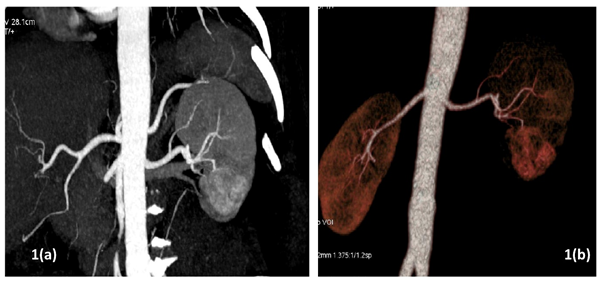

All patients underwent pre-operative contrast-enhanced computed tomography (CECT) of abdomen with renal angiography for tumour and vascular anatomy with 3D reconstruction (Figure 1). Routinely ipsilateral ureteric catheter was placed after anaesthesia. Surgical steps that were sequentially followed in all cases included ipsilateral colonic mobilization along with identification of ureter, gonadal vessels and psoas muscle; identification and mobilization of the renal artery and vein; mobilisation of the upper pole according to the need; demarcation of the tumour boundary with the help of intraoperative ultrasound; hilar clamping (renal artery and vein separately clamped); resection of the tumour; two layered renorrhaphy (Figure 2) with barbed suture with application of haemostatic agents (Gelatin granules with human thrombin and oxidised regenerated cellulose) and peri-renal drain placement. Zero-ischemia RPN were performed premeditatedly for cases with small (<4cm) cortical renal mass (predominantly exophytic) in favourable positions (lateral, lower and upper pole) and where single isolated feeder vessel was well identified (Figure 3). Ipsilateral ureteric catheter was removed routinely on 2nd post-operative day. We replaced the ureteric catheter with double-J stent where pelvicalyceal system were opened intraoperatively or tumour was larger one in vicinity to the pelvicalyceal system.

Figure 1(a) Computed Tomography with renal angiography showing left lower pole renal mass; (b) 3D reconstruction